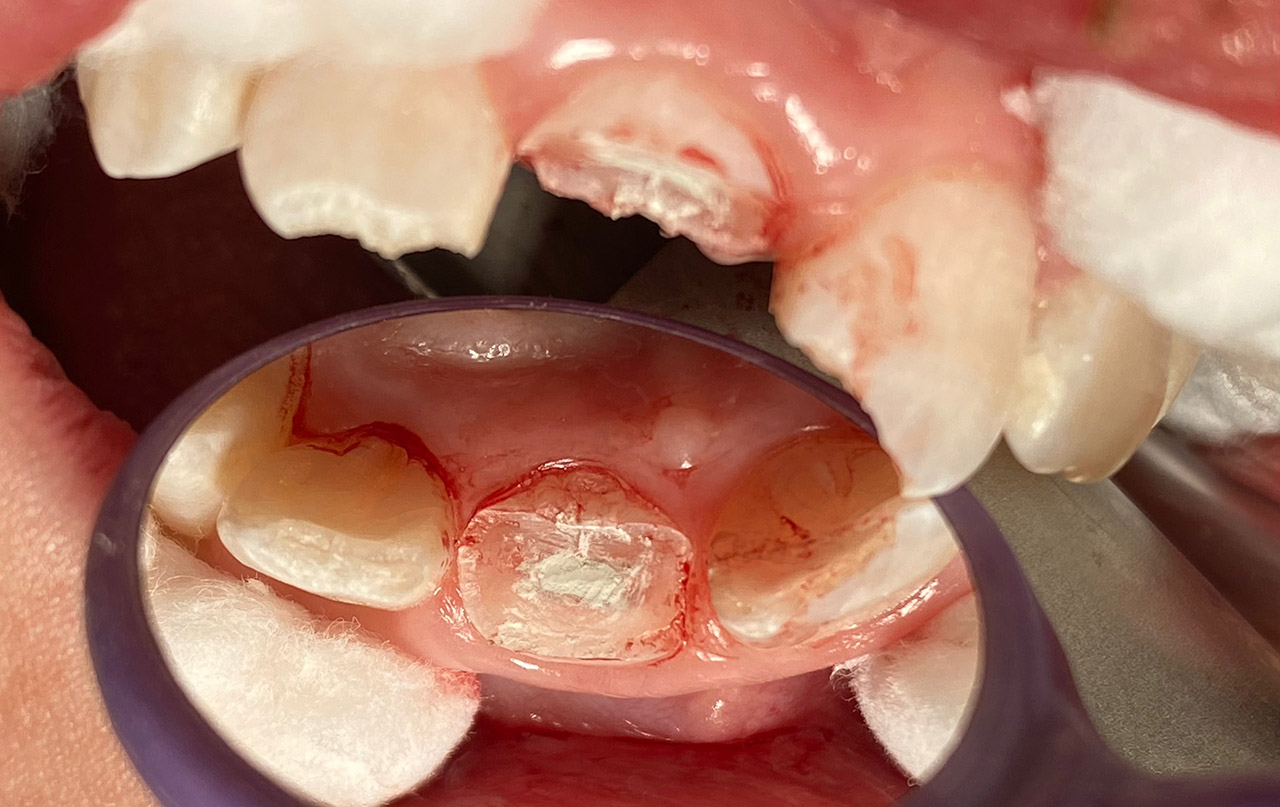

Kariestherapie:

Anamnese: tiefe Karies (Caries profunda) an beiden Oberkiefer 1. Molaren

Therapie: Zahn 16 musste Wurzelbehandelt werden, Zahn 26 konnte vital erhalten werden.

Aufbau beider Zähne in adhäsiv mit Composite/Schichttechnik.